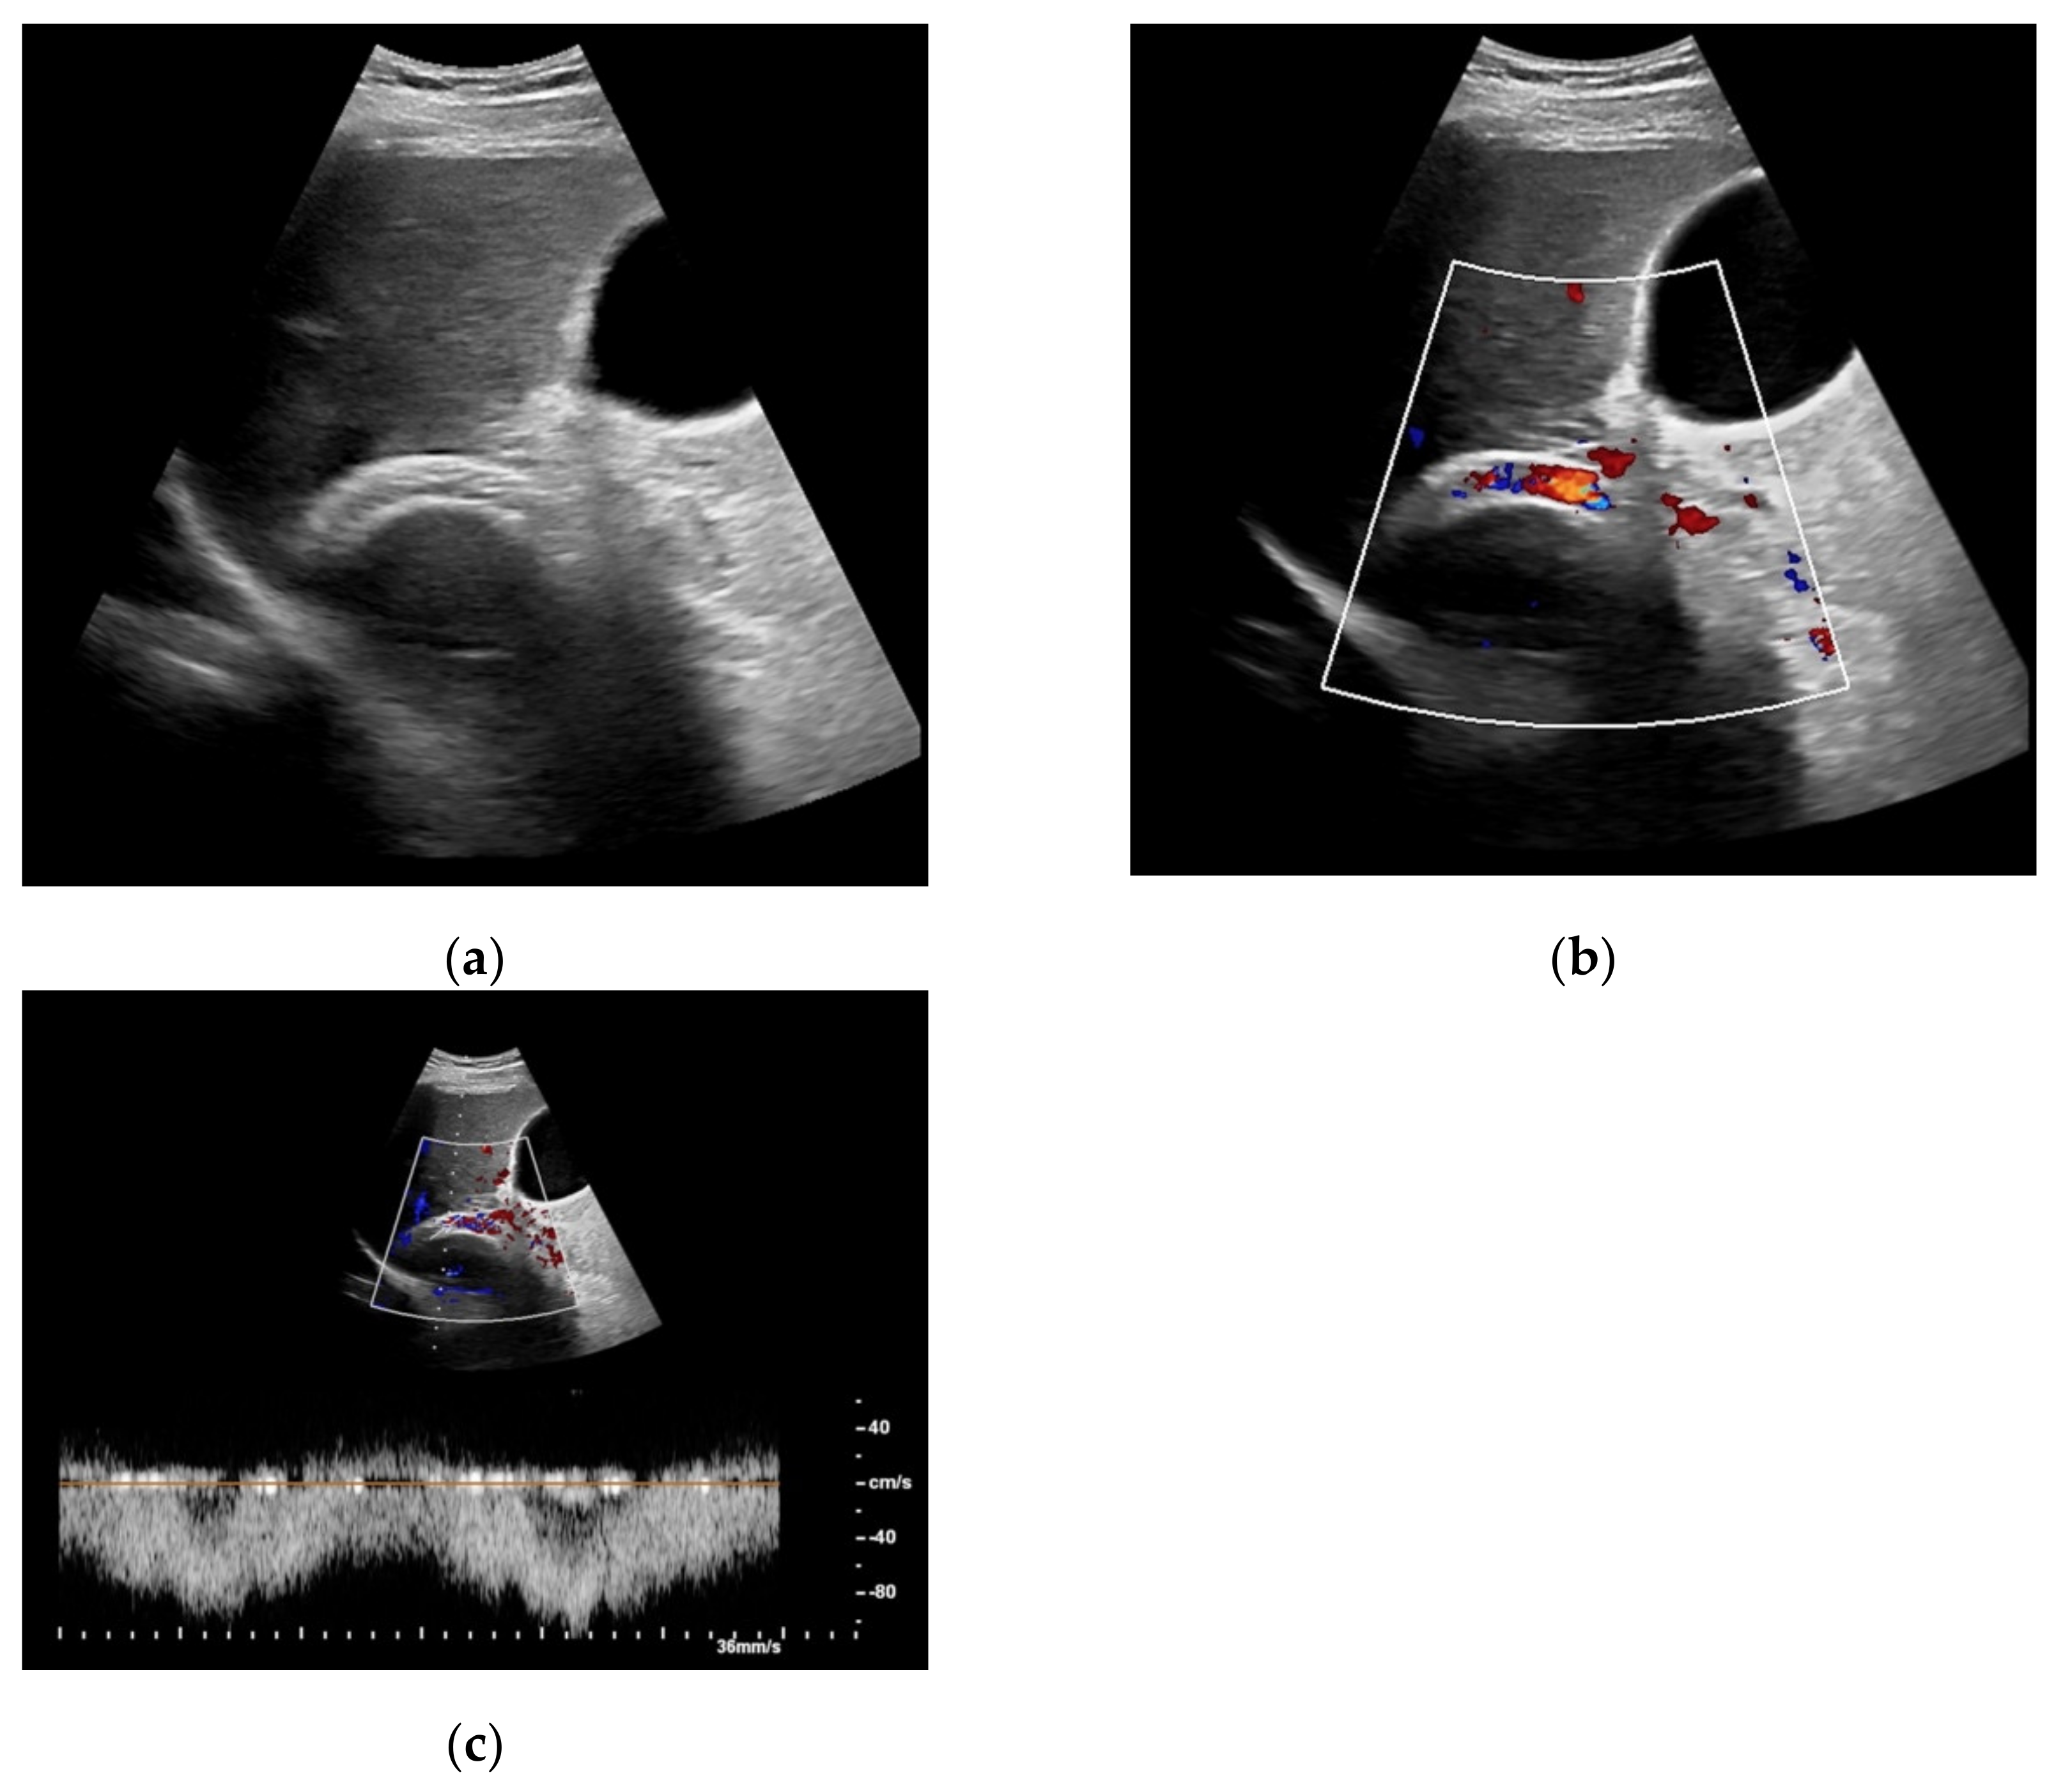

Figure 1. 65-year-old patient with regular visualization of the transjugular intrahepatic portosystemic shunt (TIPS) during B-mode (a) and adequate visualization of the TIPS in Color Doppler ultrasound (b) with inconspicuous flow and flow velocity (c).